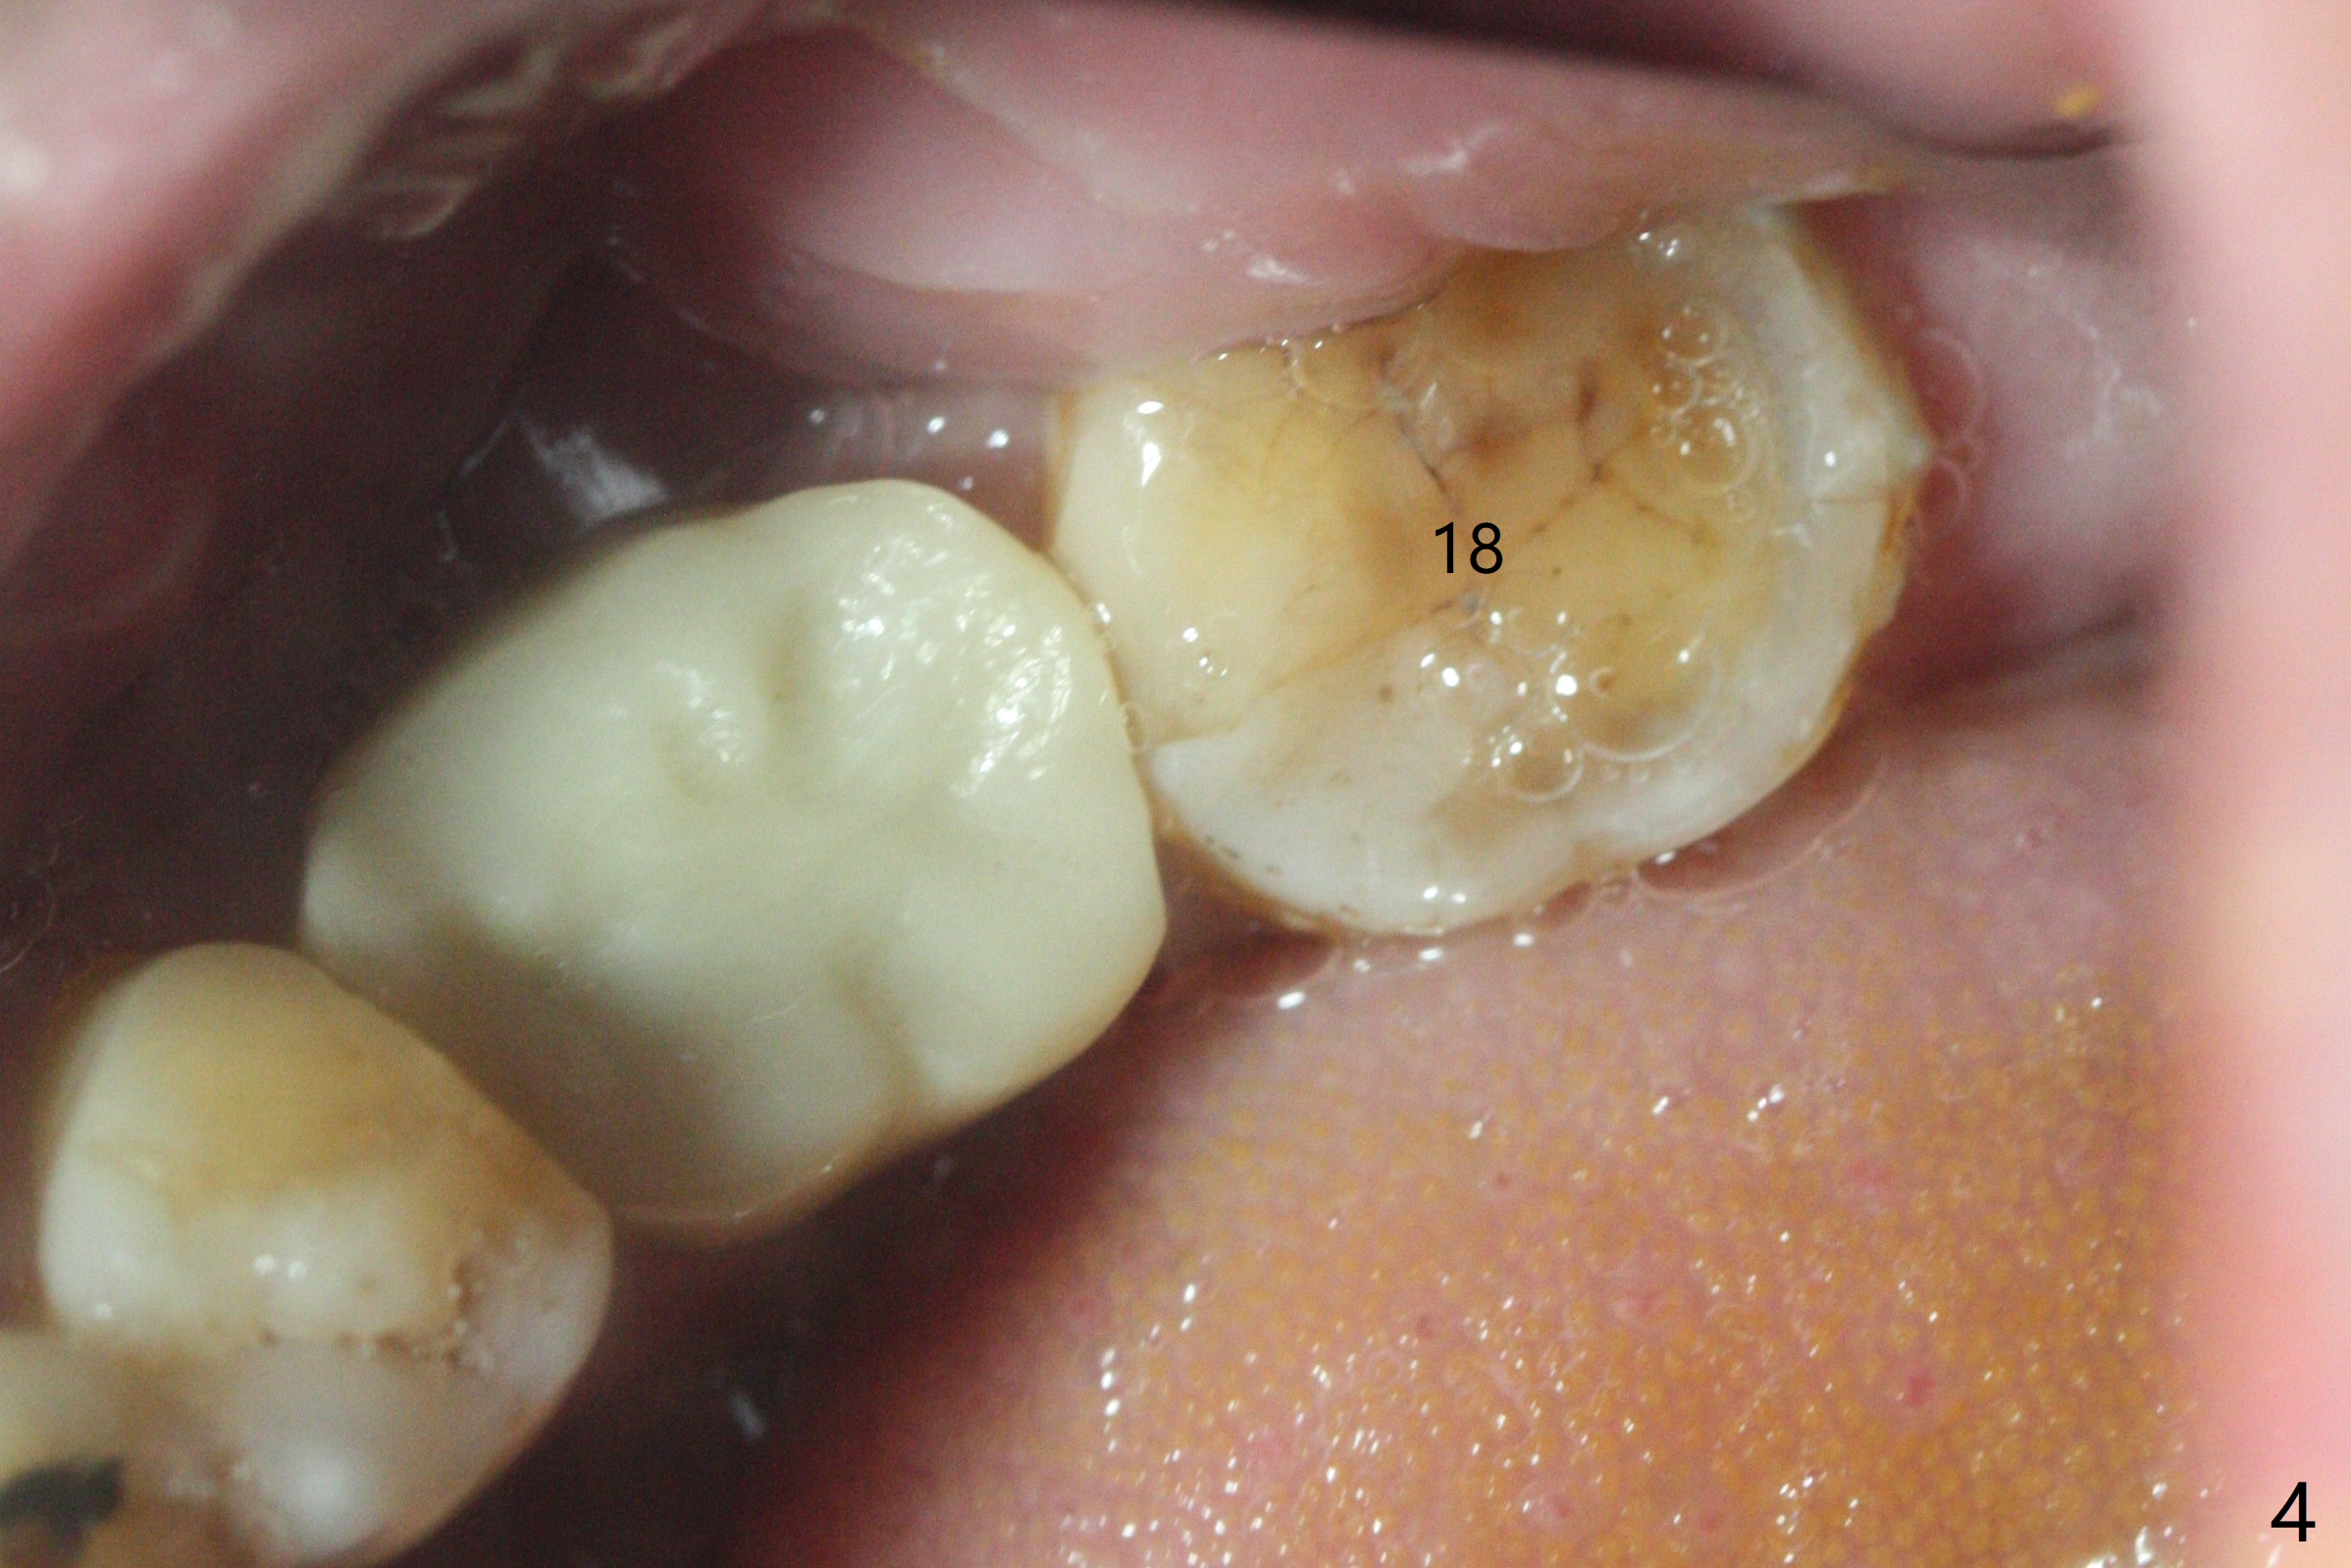

A 62-year-old man complains of food impaction around #19 implant crown one year 4 months post cementation (Fig.1-3). Before redo of the crown with poor mesial emergency profile (Fig.3 *), it appears necessary to correct the supraerupted opposing molar (Fig.1-3 downward arrow) and mesially tilted 2nd molar (Fig.3 horizontal arrow). The tooth #19 had been missing 20 years before implantation, associated with occlusal wear at #18 (Fig.4). For intrusion, composite is placed in the occlusal surface of #19 crown after roughening (Fig.5,6) with occlusal separation of the remaining dentition (Fig.6). The patient is instructed to bite on the left side as much and long as possible (even when he does not eat). Will the tooth #14 be intruded? Is the treatment sufficient?